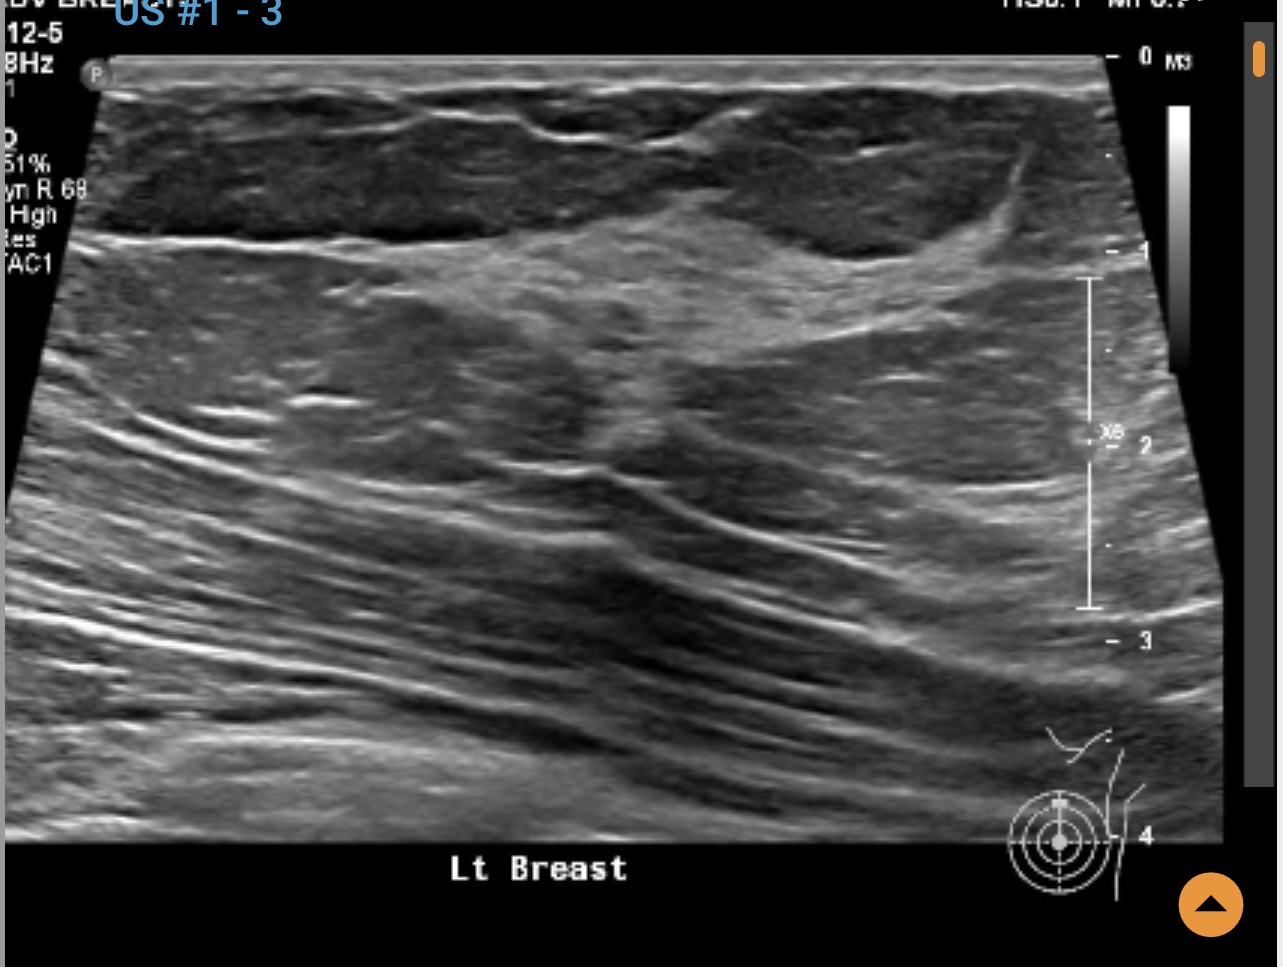

Left breast ultrasound report said no concerns. Symptoms - enlarged lymph nodes left breast, small cyst, changes in size and shape of left breast, dimples in lower left breast, pain in outer quadrant of left breast. Second opinion on ultrasound pics?